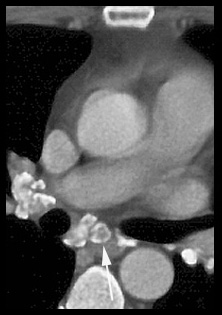

An abnormal radiograph of an asymptomatic nurse led to a CT study . CT showed these enlarged posterior mediastinal lymph nodes (arrows) next to the aorta (A). Bilateral hilar adenopathy was also shown. The posterior mediastinum is the least common site of adenopathy in sarcoidosis, but transbronchial biopsy showed nonceaseating granulomas. The nurse remains asymptomatic ten years later. |